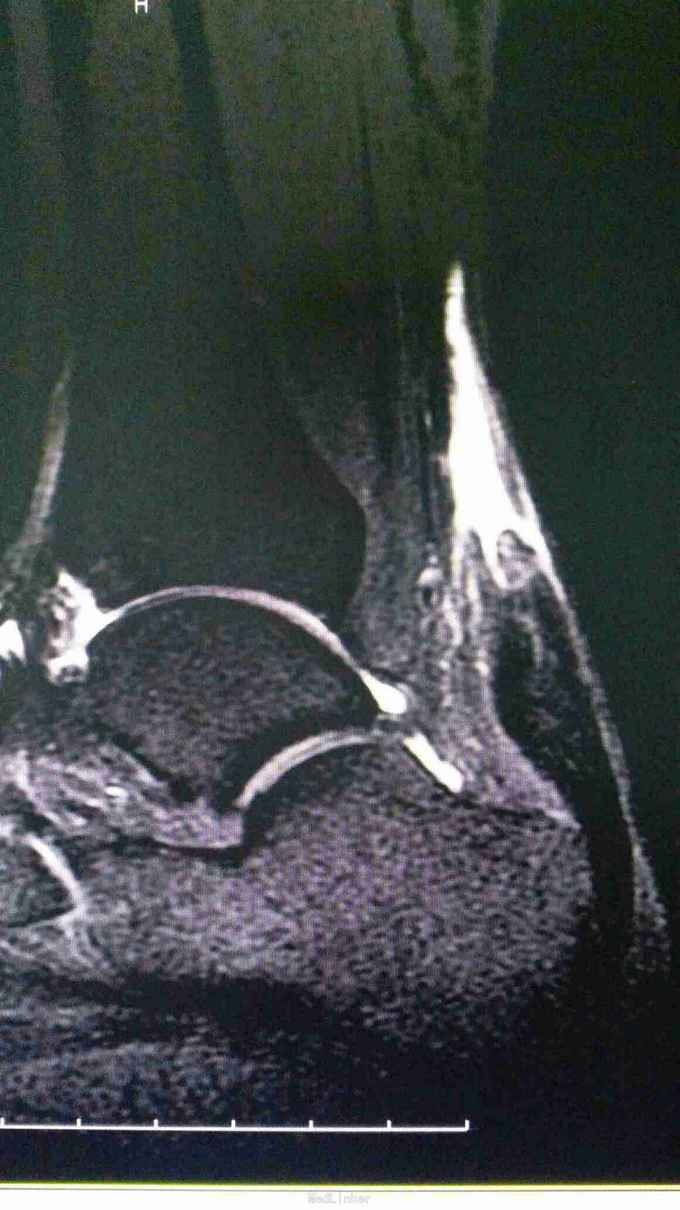

25岁男性,3月前运动受伤导致右跟疼痛,在当地按扭伤处理,现跟部疼痛,无力来诊。

跟腱止点彭大,上方空虚,压痛,提踵试验阳性。

右跟腱陈旧断裂,拟手术重建